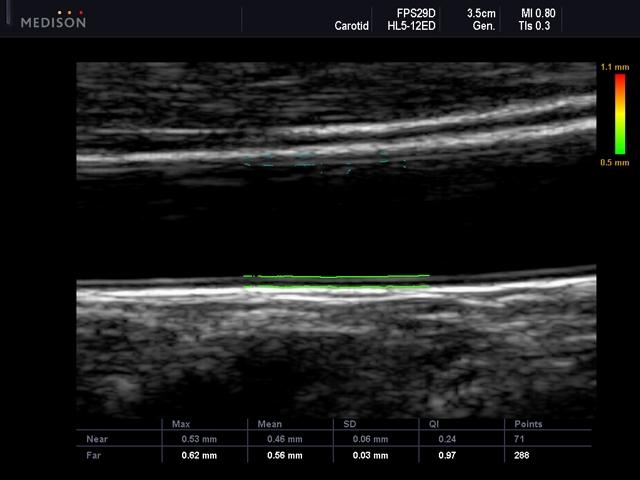

- Автоматическое измерение КИМ: AutoIMT;

Общая сонная артерия, AutoIMT